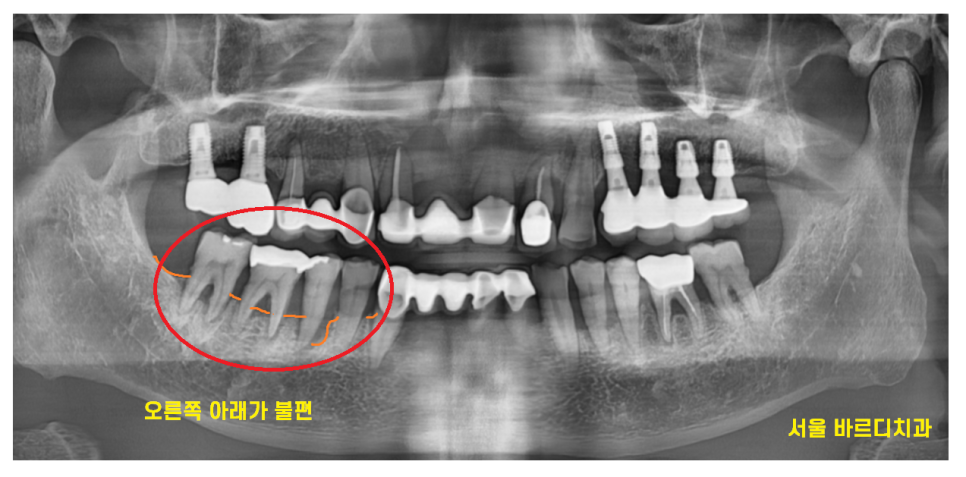

오른쪽 아래 치아가 우리~하다고 내원하신 분입니다.

하남시청치과에 방문해주셨을 때

잇몸 뼈가 많이 내려가신 상황이었습니다.

처음 x-ray를 찍어 보았을 때

기록해 두었던 내용입니다.

probing은 잇몸 깊이를 뜻합니다.

9mm , 7mm

잇몸 깊이가 깊네요~

일반적인 잇몸 깊이가 3-4mm니까

적어도 2-3배 더 깊다는 것인데요.

잇몸뼈가 많이 내려가서 그렇습니다.

mob의 경우 mobillity

(움직임)을 뜻합니다.

mob 1 < mob 3

숫자가 커질수록 더 많이 흔들린다는 뜻입니다.

그만큼 잇몸이 안좋다는 뜻인데요.

23.04.24

잇몸 깊이, 흔들림 정도를 비교해보았을 때

치아 욱신거림을 유발하는 치아

2개로 특정되었습니다.

치아 욱신거림의 원인

충치가 있어도 느껴지실 수 있지만

해당 환자분은 잇몸으로 인해

쑤시는 느낌을 받으셨네요~